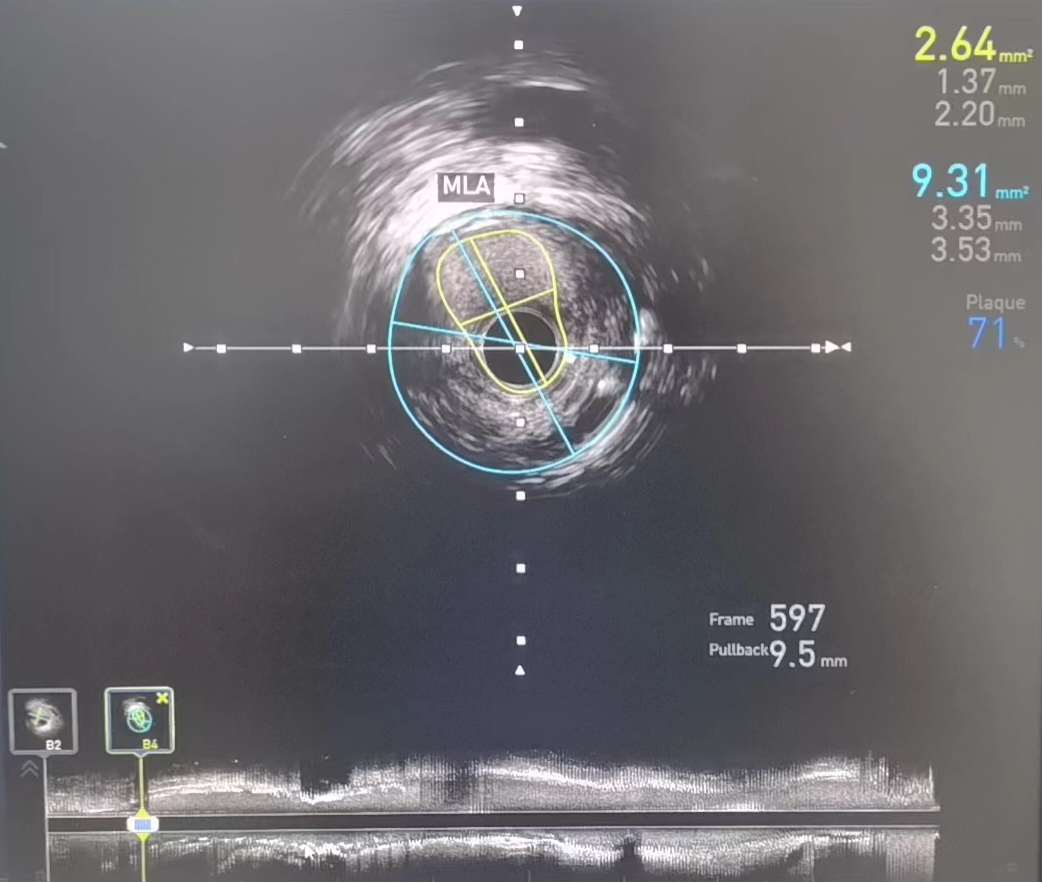

术前:IVUS-前降支管腔中段严重狭窄,最小管腔面积仅2.64mm2

术后:IVUS-前降支支架植入后

IVUS检查提示右冠中段支架以远病变加重,右冠原支架管腔畅通,经IVUS测量得出病变处MLA(管腔最小横截面积)2.64mm2,结合心电图缺血判断,该病变为患者心绞痛发作罪犯病变,对病变处实施介入治疗。

考虑无法使用造影剂进行支架定位,如何将支架定位到理想的位置,成为手术的最大难点。专家团队应用血管内超声的换能器作为路标,精确测量所需支架长度及直径,在透视下,完美将支架释放于理想位置,于右冠顺利植入支架与原有支架串联。“打通”了冠脉狭窄通路,实现了右冠脉血运的重建,再次复查IVUS显示支架位置完美,膨胀、贴壁良好,病变被完全覆盖且左冠病变无进一步处理指征,全程未使用造影剂,恢复良好。